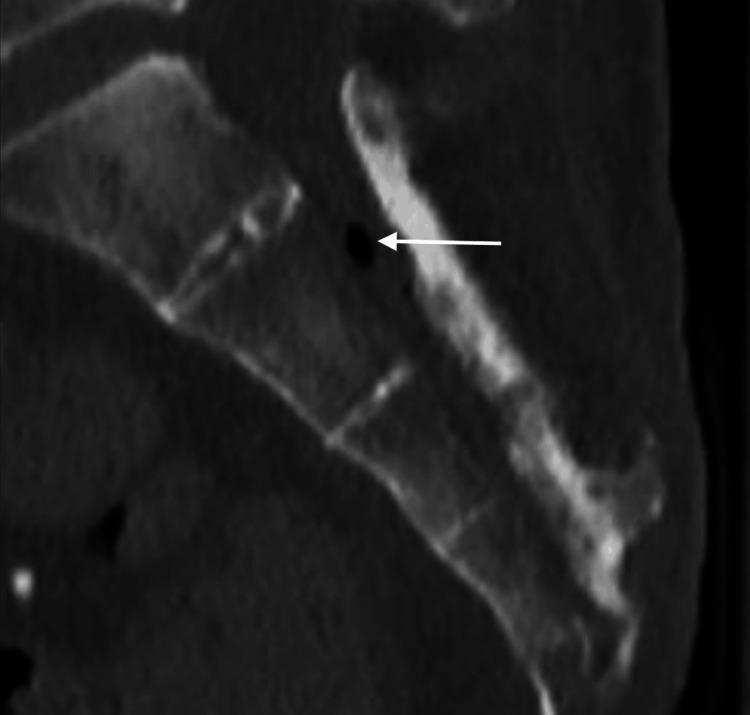

Sacral osteomyelitis is an infection of the bone that extends posterior to the pelvis at the base of the spine. This condition typically occurs in elderly or bedbound/immobile patients and is treated with wound debridement, wound care, surgery, and antibiotic therapy. In this report, a case is presented of a rare complication of sacral osteomyelitis where the infection extended through the bone into the spinal canal causing an ascending spinal canal infection. This report is meant to provide an individual example of this rare complication which can hopefully be used to improve surveillance, treatment, and outcomes of this rare condition.